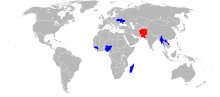

The disease is preventable with the polio vaccine; however, a number of doses are required for it to be effective.[2] The US Centers for Disease Control and Prevention recommends polio vaccination boosters for travelers and those who live in countries where the disease is occurring.[4] Once infected there is no specific treatment.[2] In 2015 polio affected less than 100 people, down from 350,000 cases in 1988.[2][5] In 2014 the disease was only spreading between people in Afghanistan, Nigeria, and Pakistan.[2] In 2015 Nigeria had stopped the spread of wild poliovirus but it reoccurred in 2016.[6][7]

Following the widespread use of poliovirus vaccine in the mid-1950s, the incidence of poliomyelitis declined dramatically in many industrialized countries. A global effort to eradicate polio began in 1988, led by the World Health Organization, UNICEF, and The Rotary Foundation.[77] These efforts have reduced the number of annual diagnosed cases by 99.9%; from an estimated 350,000 cases in 1988 to a low of 483 cases in 2001, after which it remained at a level of about 1,000 - 2000 cases per year for a number of years.[78][79] In 2015, cases decreased to 98.[5][80] Polio is one of only two diseases currently the subject of a global eradication program, the other being Guinea worm disease.[81] So far, the only diseases completely eradicated by humankind are smallpox, declared so, in 1980,[82][83] and rinderpest, likewise, in 2011.[84] A number of eradication milestones have already been reached, and several regions of the world have been certified polio-free.

In 2015, polio was believed to remain naturally spreading in only two countries, Pakistan and Afghanistan,[96][97][98][99] although it continued to cause epidemics in other nearby countries due to hidden or reestablished transmission.[100]

Afghanistan and Pakistan

This is the last remaining region with wild polio cases. Both major sides of the Afghan civil war support polio vaccination[118] and polio rates are declining rapidly in Afghanistan, with only 19 cases in 2015.[97][114]

In Pakistan there were 53 cases in 2015, the highest number for any country.[97][114] Vaccination in Pakistan is hindered by conflict and organizational problems. The militant Pakistani Taliban claims vaccination is a Western plot to sterilise local children.[119] 66 vaccinators were killed in 2013 and 2014.[120][121] Cases have dropped by 70% in 2015; reasons include Dh440 million support from the United Arab Emirates to vaccinate more than ten million children,[121][122] changes in the military situation, and arrests of some of those who attacked polio workers.[119][123]